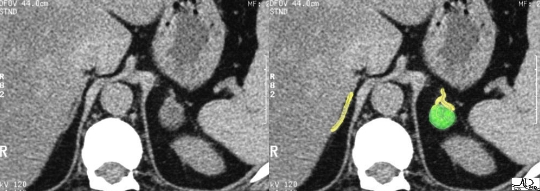

The left adrenal vein is almost always seen in cross sectional imaging lying at the apex of the gland. In this case both adrenal veins are identified (blue overlay). We have reviewed this case before which represents an aldosteronoma of the left adrenal gland. (green nodule) Courtesy of: Ashley Davidoff, M.D. |

The tiny subcentimeter green nodule at the apex of the left adrenal is a surgically proven aldosteronoma, which is a benign tumor that produces excessive aldosterone and causes hypertension. If left untreated, devastating effects of hypertension result. Courtesy of: Ashley Davidoff, M.D. |

These “in-phase” and “out-of-phase” T1-weighted images focus on the normal right gland. The left gland cannot be visualised on these images. On the “in-phase” sequence (first image), the adrenal is almost isointense with the liver while on the “out-of-phase” sequence, the gland darkens slightly. Courtesy of: Ashley Davidoff, M.D. |